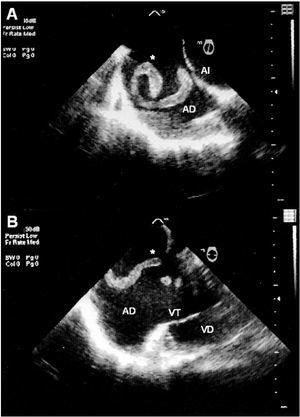

Figura 2. Ecocardiograma transesofágico en el que se puede apreciar el trombo en toda su extensión (A) y cómo al moverse da la impresión de ser varios trombos o encontrarse fragmentado (B). AD: aurícula derecha; AI: aurícula izquierda; (*): trombo; VD: ventrículo derecho; VT: válvula tricúspide.

Se trata de un varón de 71 años con antecedentes de hipertensión arterial, dislipemia, linfoma no hodgkiniano, infarto anterior 4 años antes, y fibrilación auricular permanente. Ingresa por disnea de reposo sin dolor torácico, presentando posteriormente episodios sincopales. En el ecocardiograma transtorácico (ETT) del ingreso se documentó disfunción ventricular izquierda severa por acinesia anteroseptal y apical, con dilatación, disfunción ventricular derecha e hipertensión pulmonar. Se realizó monitorización Holter ante la sospecha de arritmias ventriculares secundarias a la cicatriz del infarto previo, donde se objetivaron episodios de taquicardia ventricular no sostenida (TVNS) (fig. 1). Después de iniciar el tratamiento con amiodarona no se documentan nuevos episodios de TVNS ni síncopes, pero al alta de la Unidad de Cuidados Intensivos presenta disnea súbita con taquipnea e hipocapnia. En un nuevo ETT se apreció una imagen en movimiento en el interior de la aurícula derecha, por lo que se completó el estudio con un ecocardiograma transesofágico (ETE), observándose una masa serpinginosa en el interior de la aurícula derecha, móvil y alargada, compatible con un trombo de movimiento aleatorio y forma de «molde venoso» (fig. 2). Dada la estabilidad hemodinámica y la comorbilidad se decidió tratamiento con heparina sódica por vía intravenosa. El eco-doppler de miembros inferiores fue compatible con trombosis venosa profunda. El ETE realizado 10 días después no detectó la existencia de trombos, aunque tampoco se puede descartar la migración total o parcial del mismo. La evolución posterior del paciente fue desfavorable con insuficiencia cardíaca congestiva refractaria al tratamiento médico, que terminó siendo éxitus.